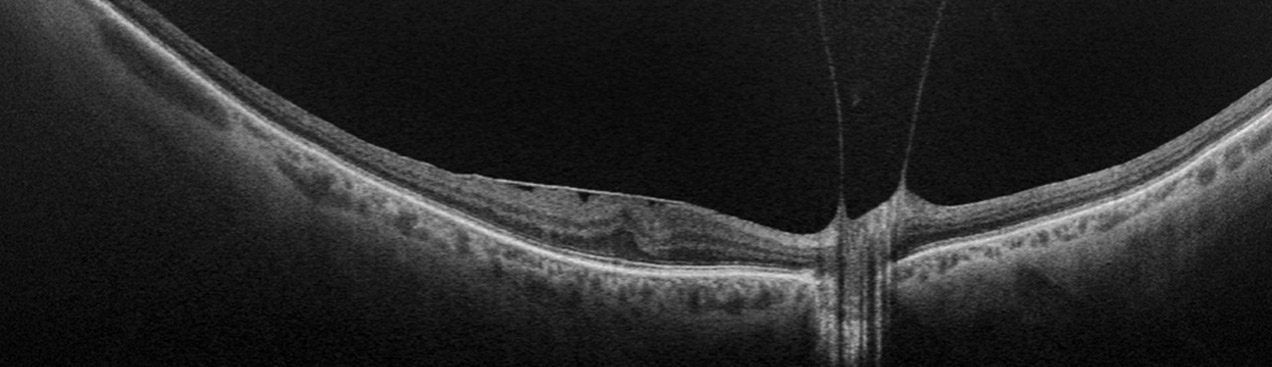

optomap guided OCT enhances patient management by combining ultra-widefield imaging with OCT guidance to deliver a more complete view of retinal health. This approach helps clinicians detect critical findings earlier, reduce the risk of misdiagnosis, and make more informed treatment decisions. By integrating widefield capture with guided OCT scans, practices can streamline workflow, increase diagnostic confidence, and provide patients with a higher level of care and personalized management.

Optos offers multimodal imaging with all ultra-widefield devices. Having both ultra-widefield and four images captured in less than one second has been shown to enhance pathology detection and disease management as well as improve practice and clinic flow. Ultra-widefield multimodal imaging is important across all access points of patient care - screening, detection, diagnosis, and treatment.